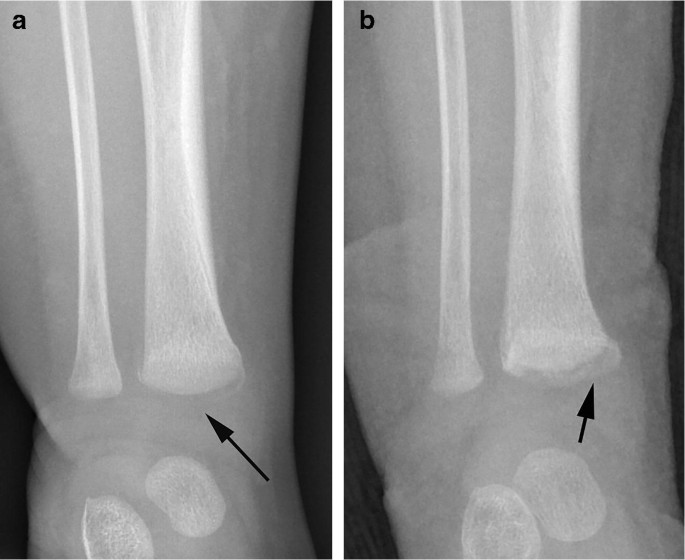

radiological dating of fractures and even less relating fractureagetochildabuse . Themostcomprehensivereview is byO'ConnorandCohen .' . . . Fresh fractures , including metaphyseal fractures , have sharply defined margins . With the development of an osteoclastic response to necrotic bone the fracture ends

Radiologic dating of fractures is an inexact science . Most radiologists date fractures on the basis of their personal clinical experience, and the literature provides little consistent data to act as a resource . There is an urgent need for research to validate the criteria used in the radiologic dating of fractures in children younger than 5 years .

It is known that it is more difficult to date certain fractures over others including metaphyseal fractures and skull fractures . Experienced paediatric radiologists are usually instructed to assist in such cases as they have the skill and up to date knowledge/ experience to date the fractures are easily as possible .

These metaphyseal abnormalities were identified from postmortem radiogra-phy and correlated with microscopy . The au-thors concluded the metaphyseal alterations represented partial or complete planar micro- fractures that transected the primary spongio-sa adjacent to the growth plate . These micro- fractures usually resembled a "bucket-handle"

Specific fractures . A number of fractures have been recognised as highly specific to non-accidental injuries (rather than accidental injury) . They include: metaphyseal fracture (so-called bucket handle fracture or corner fracture ) present in up to 39-50% of abused infants <18 months; said to be virtually pathognomonic of NAI; rib fractures